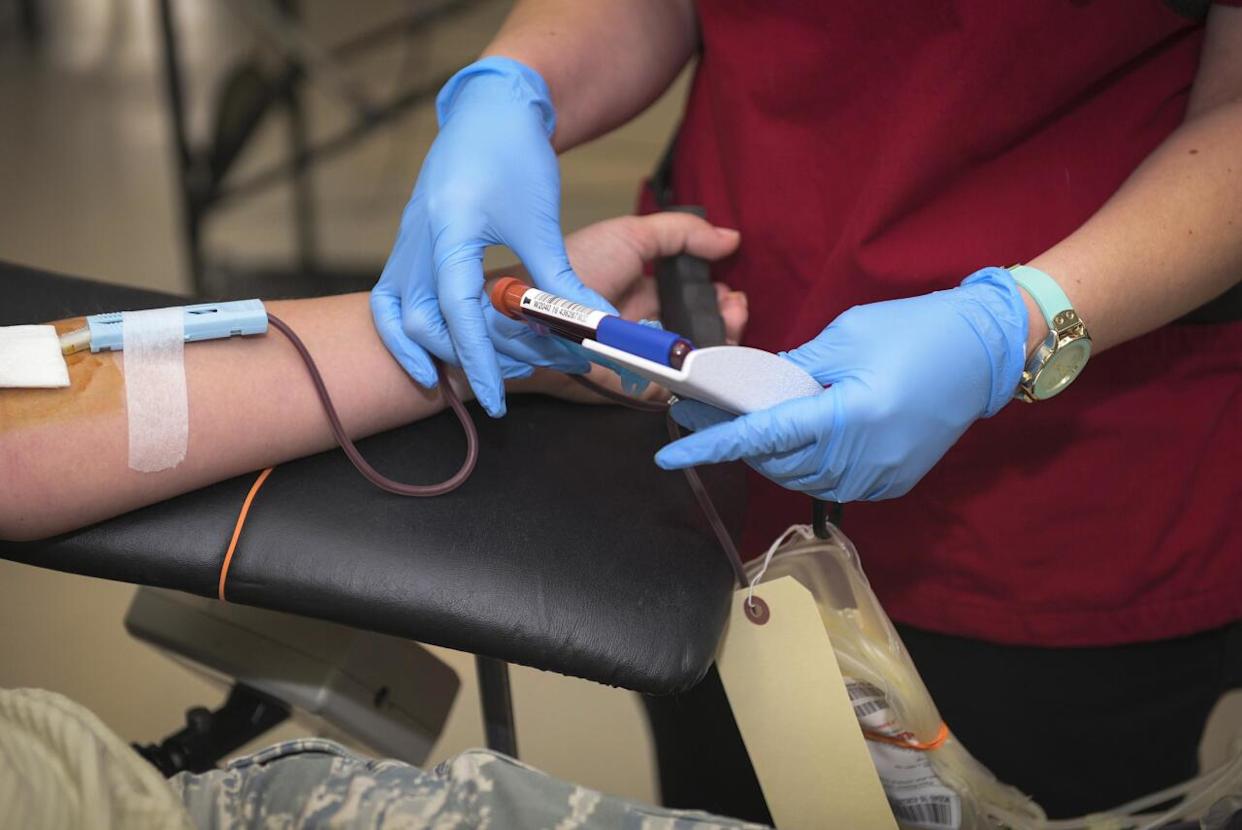

Deoxygenated blood looks blue

Possibly confused by the fact that some of your veins appear blue, many schoolchildren believe that blood only turns red when it’s exposed to oxygen. However, this just isn’t true.